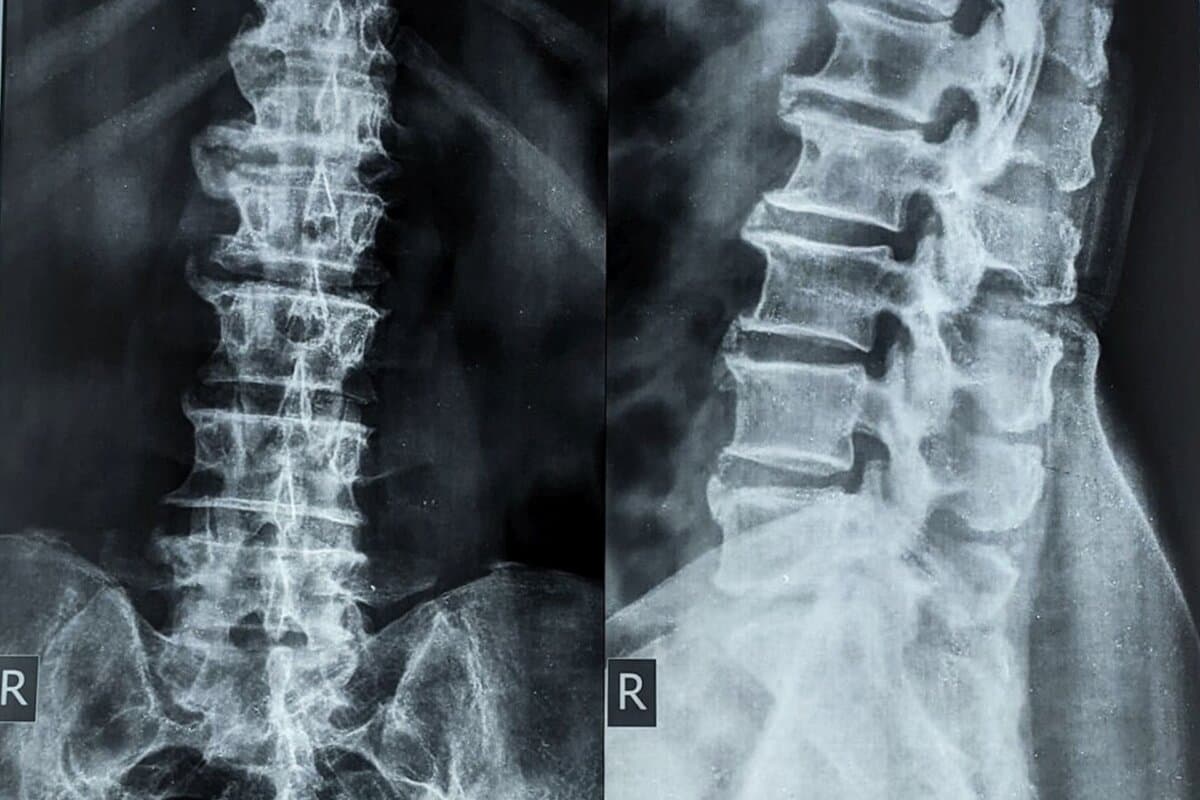

Rheumatoide Arthritis: Orale oder intraartikuläre Glukokortikoide?

Die frühe rheumatoide Arthritis muss so rasch wie möglich in Remission gebracht werden – das fordern die rheumatologischen Fachgesellschaften. Doch welche Strategie dafür am besten geeignet ist, bleibt unklar. Eine Analyse deutet darauf hin, dass Gelenkspritzen kombiniert mit einer Tripletherapie Vorteile bieten könnten.